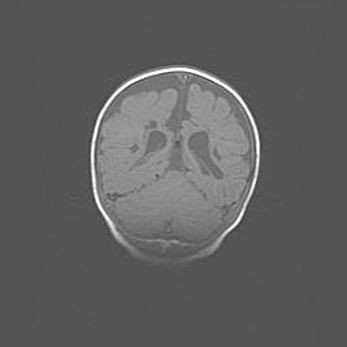

Наружная гидроцефалия с возможной атрофией височных областей.

Возраст: 28 дней

Вес: 3670 г

Пол: мужской

Окружность головы: 38 см

Срок гестации: 40 недель

Гидроцефалия головного мозга у новорожденных – это заболевание, которое характеризуется скоплением избыточного количества спинномозговой жидкости в желудочковой системе головного мозга в результате затруднения её перемещения от места выработки к месту поглощения в кровеносную систему или вследствие нарушения абсорбции. При открытой наружной форме гидроцефалии у новорожденных расширяются и переполняются субарахноидные пространства.

При нормотензивных  формах,  которые,  как  правило,  являются  следствием  перенесенных ишемических  повреждений  паренхимы  мозга,  возможно  сочетание микроцефалии  с нормотензивной гидроцефалией. В основе данных изменений лежит атрофия больших полушарий с преимущественной  локализацией  в  лобно-височных  областях.